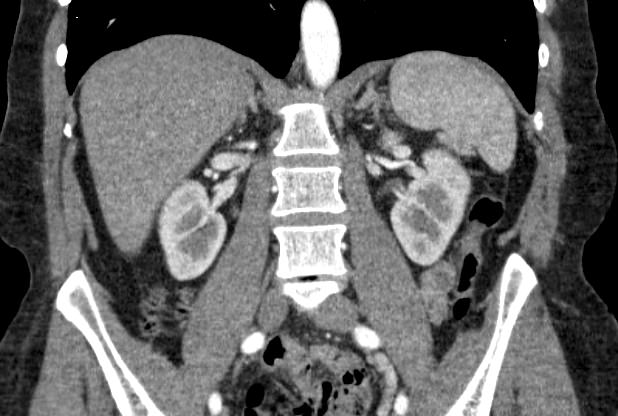

Мультиспиральная компьютерная томография (МСКТ) брюшной полости и забрюшинного пространства относится к современным лучевым методам исследования, с помощью которого можно оценить состояние органов брюшной полости (печени, желчного пузыря, поджелудочной железы, селезенки), забрюшинного пространства с расположенными в нем почками, надпочечниками, мочеточниками и прилегающих к ним кровеносных сосудов и лимфатических узлов.

С помощью мультиспиральной компьютерной томографии проводятся послойные рентгеновские снимки исследуемой области с толщиной среза от 0,5 мм. Затем полученные данные преобразуются в цифровые трехмерные модели органов и систем в мельчайших подробностях.

При подозрении на опухоли, воспалительные процессы, гнойные очаги назначается КТ брюшной полости и забрюшинного пространства с внутривенным болюсным контрастированием. Для этого пациенту внутривенно вводится рентгеноконтрастное вещество на основе йода. Благодаря усиленному кровоснабжению, которое обычно наблюдается в патологических очагах, препарат накапливается в структуре патологических образований и помогает врачу-рентгенологу выявить изменения внутренних органов.

Метод контрастирования помогает максимально точно выявить очаг патологии уже на начальной стадии, а также установить его локализацию, точные размеры, форму и особенности кровоснабжения. Возможности мультиспиральной компьютерной томографии позволяют выполнить своевременную диагностику заболеваний внутренних органов, от чего напрямую зависит эффективность лечения.